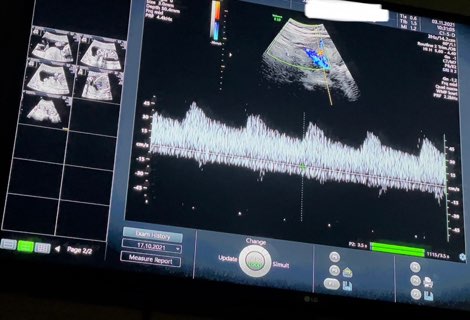

検診で「胎盤につながる血管2本の血管のうち1本が細く、赤ちゃんに十分に栄養が届かない可能性がある」と言われ、アスピリンを服用しています。3週間服用しましたがあまり改善されていませんでした。

そのうちママさん→赤ちゃんに向かう血管が細めなんですね。